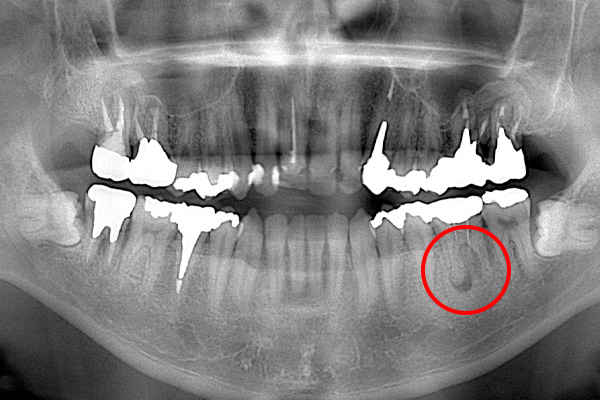

それは歯の先に枝分かれが多く存在し、そこにばい菌が入り込んで難治性となっているからです。ではその場合どうするのか?外科治療をします。その枝分かれの部分を切り落とすのです。今回はその前後のレントゲンの写真をお見せします。

| 根の中の薬が十分に充填されておらず、根の先が周りと比べて黒くなっており、炎症があると判断できます。 | 根の中にしっかりとお薬を緊密に充填しましたが、まだ根の先に黒くなっている部分があります。 |

| 根の中にお薬を充填した後のCT画像。やはり根の先に黒い影があるのがわかります。 |

| 治療方針 | 5年ほど前に他院で治療した歯が噛むと痛いということでした。初診時のパノラマレントゲンを診てみると、根管治療がかなり雑にされており、その上にかぶせ物がはいっている状態でした。ですので、まずはかぶせ物をはずし、根管治療のやり直しを行います。 その後、感染物質を取り除くために、根尖切除も治療計画に含めました。根管治療のみで根の先の炎症がなくなれば根尖切除は行わない計画にしました。 |